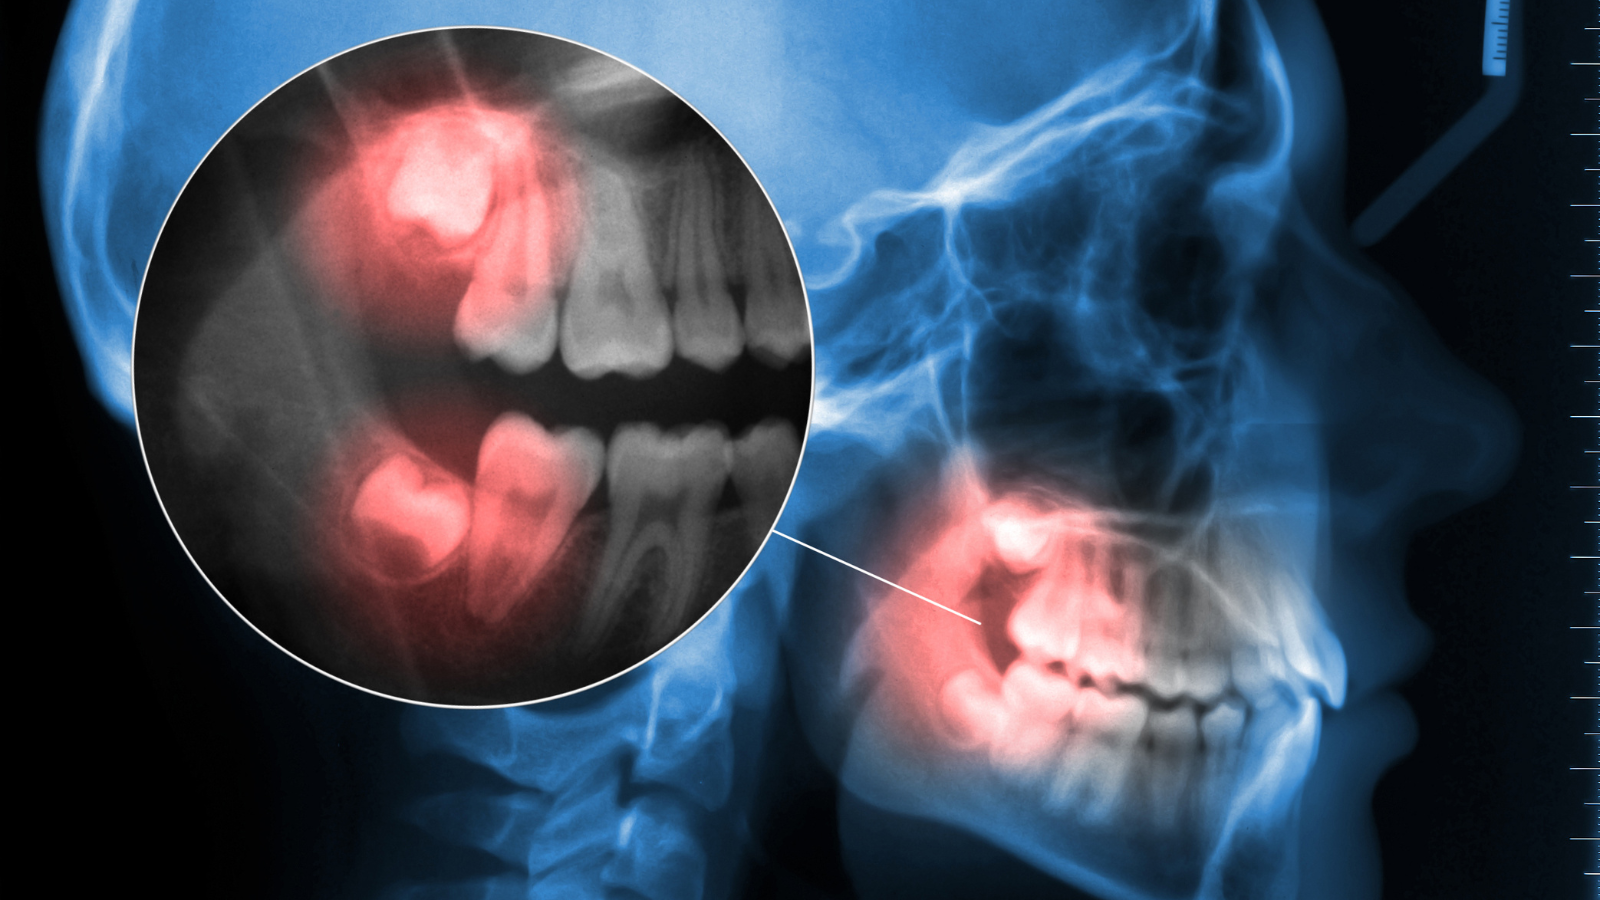

- Radiografías: Las radiografías dentales son herramientas cruciales para evaluar la posición de las muelas del juicio y la presencia de pericoronaritis. Estas imágenes proporcionan una visión detallada de la estructura ósea y permiten al/la odontólogo/a identificar la presencia de infección o inflamación alrededor de la muela del juicio.